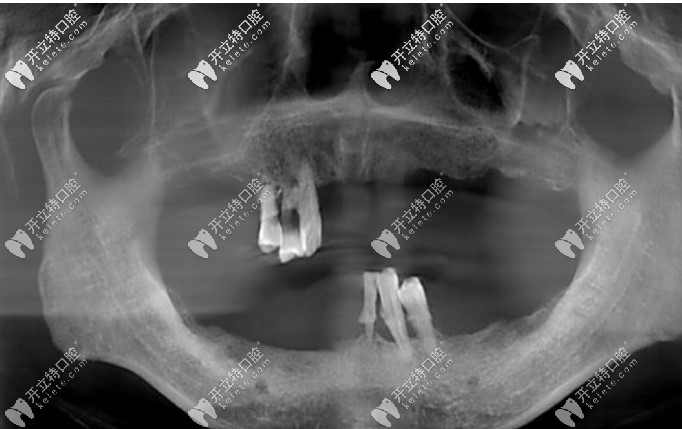

設(shè)備環(huán)境:占地1100平方米,配備CBCT、數(shù)字化掃描儀等設(shè)備,嚴(yán)格消毒流程,候診區(qū)溫馨舒適,兒童診室趣味貼心。

1. 種植中心:進(jìn)口系統(tǒng)+微創(chuàng)

• 技術(shù)亮點(diǎn):開展數(shù)字化導(dǎo)板種植、即刻負(fù)重等技術(shù),創(chuàng)傷小、。